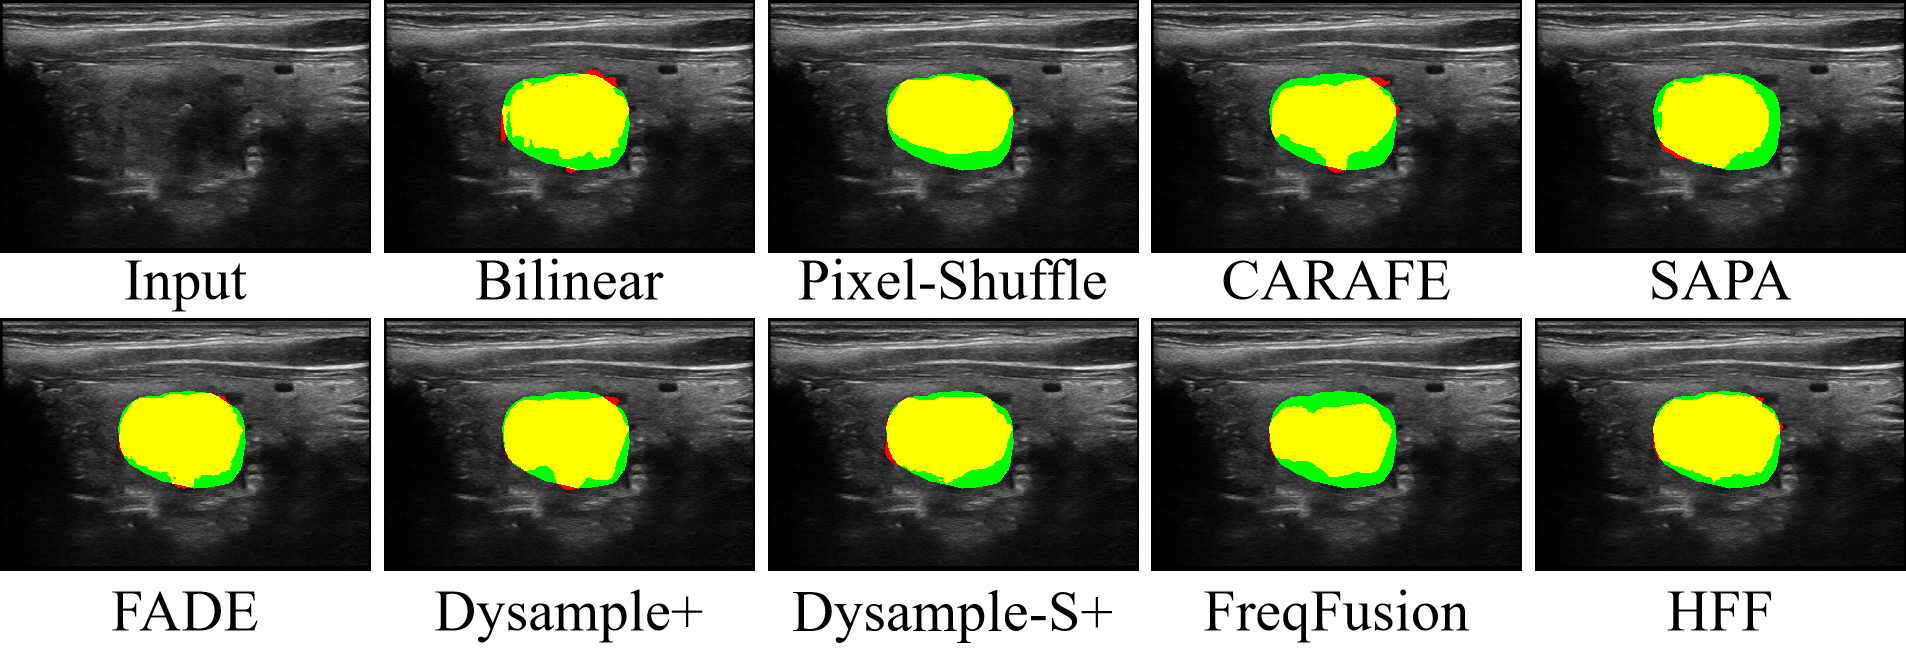

5.2 Comparison of HFF with other feature fusion module

The HFF module was replaced with nine fusion methods, which are shown in Table 7. Our method achieved the highest DSC, IoU, and recall scores, demonstrating the most accurate alignment with the ground-truth masks, especially in the foreground regions. Among these SOTA methods, CARAFE, FADE, Dysample+, and FreqFusion also achieve strong performance, ranking just below our proposed method. CARAFE and FADE benefited from capturing high-resolution structures. Dysample+ mitigated inconsistencies in potential features using a refined upsampling strategy. FreqFusion combined the advantages of both low-level and high-level feature representations via frequency-aware fusion and adaptive resampling to effectively integrate global and local features. Inspired by these methods and aiming to increase the utilization rate of HF information, we proposed the HFF module, which integrates adaptive wavelets that are both HF-sensitive and noise-unaware to facilitate the efficient fusion of multiresolution features, with a particular emphasis on high-resolution detail components, ultimately leading to optimal performance. The typical visualization results are shown in Fig. 7. To demonstrate the effectiveness of the HFF module in terms of addressing boundary displacement issues in ultrasound segmentation tasks, the fused feature maps generated from both bilinear interpolation and the proposed HFF module were visualized, as shown in Fig. 8. The first row presents the visualization of a single feature map. The next two rows show BGR images generated by mapping the first three principal components after applying principal component analysis to the feature map. It can be seen that our method produces clearer boundary delineation and cleaner background regions. The HFF module could effectively suppress the interfering HF components using the AWLF mechanism, thereby reducing noise and intraclass inconsistency. Furthermore, it could enhance the relevant HF features through the AWHF mechanism, resulting in sharper and more accurate boundary representations.